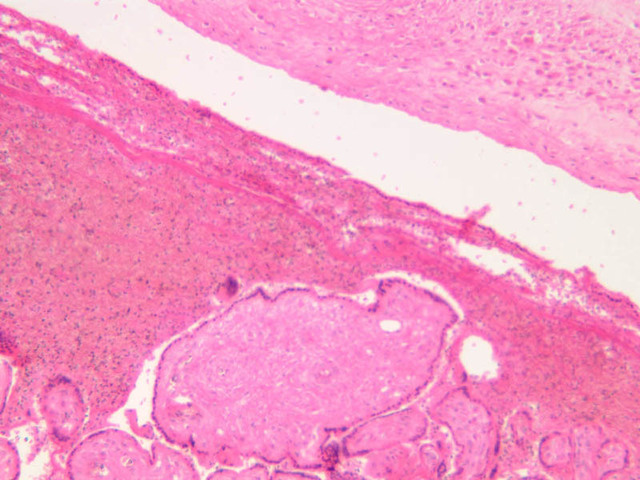

The endometrium of the cervical canal does not slough during the menstrual phase. The glands in this region are relatively large and extensively branched. They are lined by a tall simple columnar epithelium very active in the secretion of mucus. Occasionally these glands become blocked forming Nabothian cysts. The transition of the epithelium of the cervix to that of the vagina is abrupt and is in the region of the external os. At this point, the cervical simple columnar is replaced by the vaginal stratified squamous epithelium (slide B-98 [2.5x-labeled, 10x, 20x, 40x] [2.5x, 10x, 20x, 40x]). This is an area which is commonly inflamed as well as a primary location of cervical cancer.